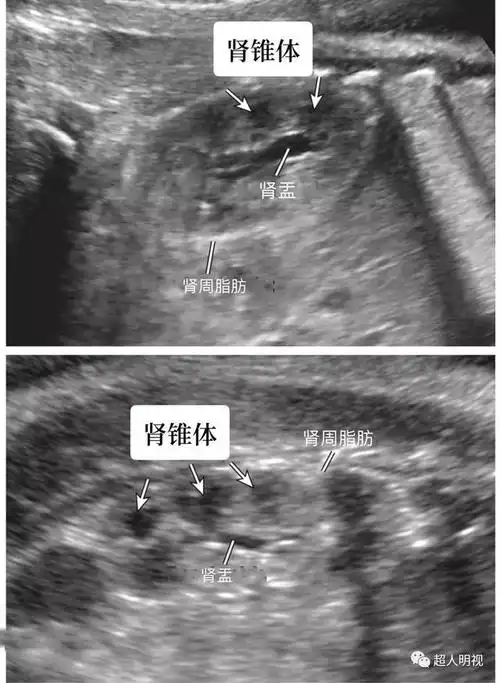

胎儿肾脏解剖及大小